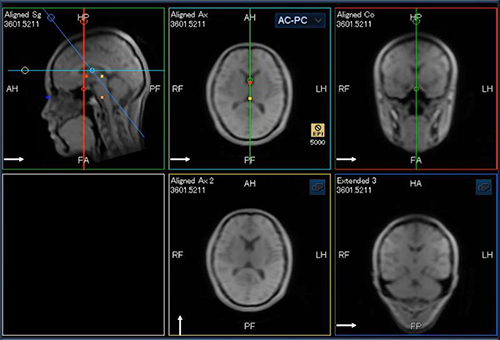

また,頭部位置決めアシスト機能NeuroLineにOMおよびAC-PC断面を追加したNeuroLine+や(図3),脊椎位置決めアシスト機能SpineLineを搭載し,複雑な位置決めにおける術者の負担軽減と操作時間の短縮を実現する。

図3